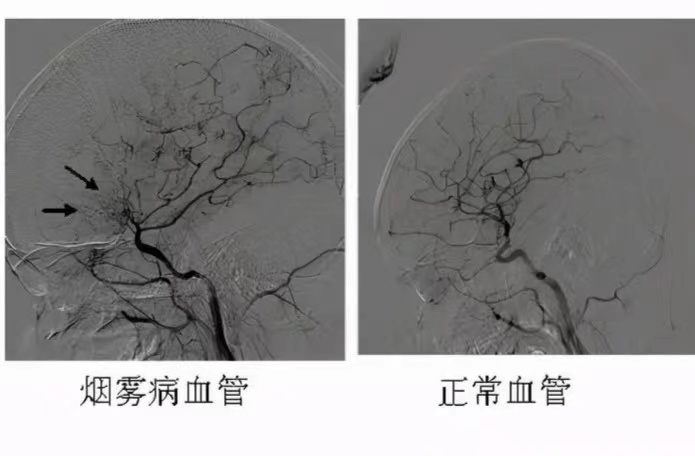

烟雾病目前难以完全治愈,但可通过治疗缓解症状并降低风险烟雾病的本质与治疗难点烟雾病是一种以颈内动脉末端及大脑前中动脉起始部慢性进行性狭窄或闭塞为特征的脑血管疾病,因血管造影显示脑底异常血管网形似“烟雾”而得名其核心病理改变为脑动脉发育异常或进行性狭窄,导致脑组织供血不足,易引发;药物治疗无效药物治疗对烟雾病的症状治愈没有效果,因此一旦发现烟雾病,应尽早考虑手术治疗烟雾病可能导致的严重后果烟雾病可能导致脑出血脑缺血脑梗等严重后果,甚至可能危及生命其中,脑出血是烟雾病死亡的主要原因病情发展迅速烟雾病患者的病情会在不进行治疗的情况下迅速发展,尤其是缺血;综上,烟雾病虽无法根治,但通过个体化手术方案与终身健康管理,多数患者可获得良好预后,生活质量接近常人早期诊断规范治疗是改善预后的关键;烟雾病目前难以实现完全治愈,但可通过现代医疗技术有效控制病情发展烟雾病是一种以双侧颈内动脉末端及其分支进行性狭窄或闭塞为特征,并在颅底形成异常血管网的慢性脑血管疾病其病理机制涉及血管发育异常和血流动力学改变,导致脑供血不足或异常血管破裂风险增加理论上,由于疾病本身的进展性和血管结构的。